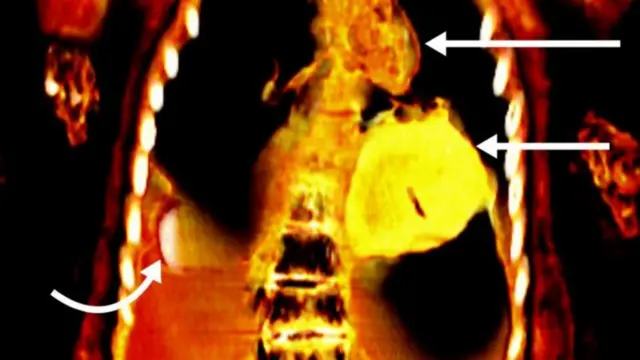

ਤਸਵੀਰ ਸਰੋਤ, S.N. SALEEM, S.A. SEDDIK, M. EL-HALWAGY

ਸਕੈਨ ਤੋਂ ਪਤਾ ਲੱਗਿਆ ਹੈ ਕਿ ਮ੍ਰਿਤਕ ਪ੍ਰਾਚੀਨ ਮਿਸਰ ਦੇ ਉੱਚ ਵਰਗ ਤੋਂ ਸੀ ਕਿਉਂਕਿ ‘ਉਸ ਦੇ ਦੰਦ ਅਤੇ ਹੱਡੀਆਂ ਸਿਹਤਮੰਦ ਸਨ ਅਤੇ ਕੁਪੋਸ਼ਣ ਦਾ ਕੋਈ ਸੰਕੇਤ ਨਹੀਂ ਸੀ।’

ਉਸ ਦੀ ਲਾਸ਼ ਨੂੰ ਉੱਚ ਪੱਧਰੀ ਮਮੀ ਪ੍ਰਕਿਰਿਆ ਰਾਹੀਂ ਸੰਜੋਇਆ ਗਿਆ ਸੀ। ਇਸ ਤਹਿਤ ਦਿਮਾਗ ਅਤੇ ਸ਼ਰੀਰ ਦੇ ਅੰਦਰ ਦੇ ਹੋਰ ਅੰਗਾਂ ਨੂੰ ਕੱਢ ਲਿਆ ਗਿਆ ਸੀ।

ਇਸ ਅੱਲ੍ਹੜ ਦਾ ਖ਼ਤਨਾ ਨਹੀਂ ਹੋਇਆ ਸੀ। ਤਸਵੀਰਾਂ ਤੋਂ ਪਤਾ ਲੱਗਿਆ ਹੈ ਕਿ ਪੱਟੀਆਂ ਦੇ ਹੇਠਾਂ ਇਸ ਨੌਜਵਾਨ ਦੇ ਸ਼ਰੀਰ ਵਿੱਚ ਦੋ ਉਂਗਲਾਂ ਦੀ ਇੱਕ ਚੀਜ਼ ਲਿੰਗ ਦੇ ਕੋਲ ਸੀ।

ਮ੍ਰਿਤਕ ਦੇ ਮੂੰਹ ਵਿੱਚ ਜੀਭ ਵੀ ਸੋਨੇ ਦੀ ਸੀ ਅਤੇ ਛਾਤੀ ਦੇ ਹੇਠਾਂ ਦਿਲ ਦੀ ਸ਼ਕਲ ਦਾ ਸੋਨੇ ਦਾ ਬਣਿਆ ਇੱਕ ਝੀਂਗਾ ਸੀ।